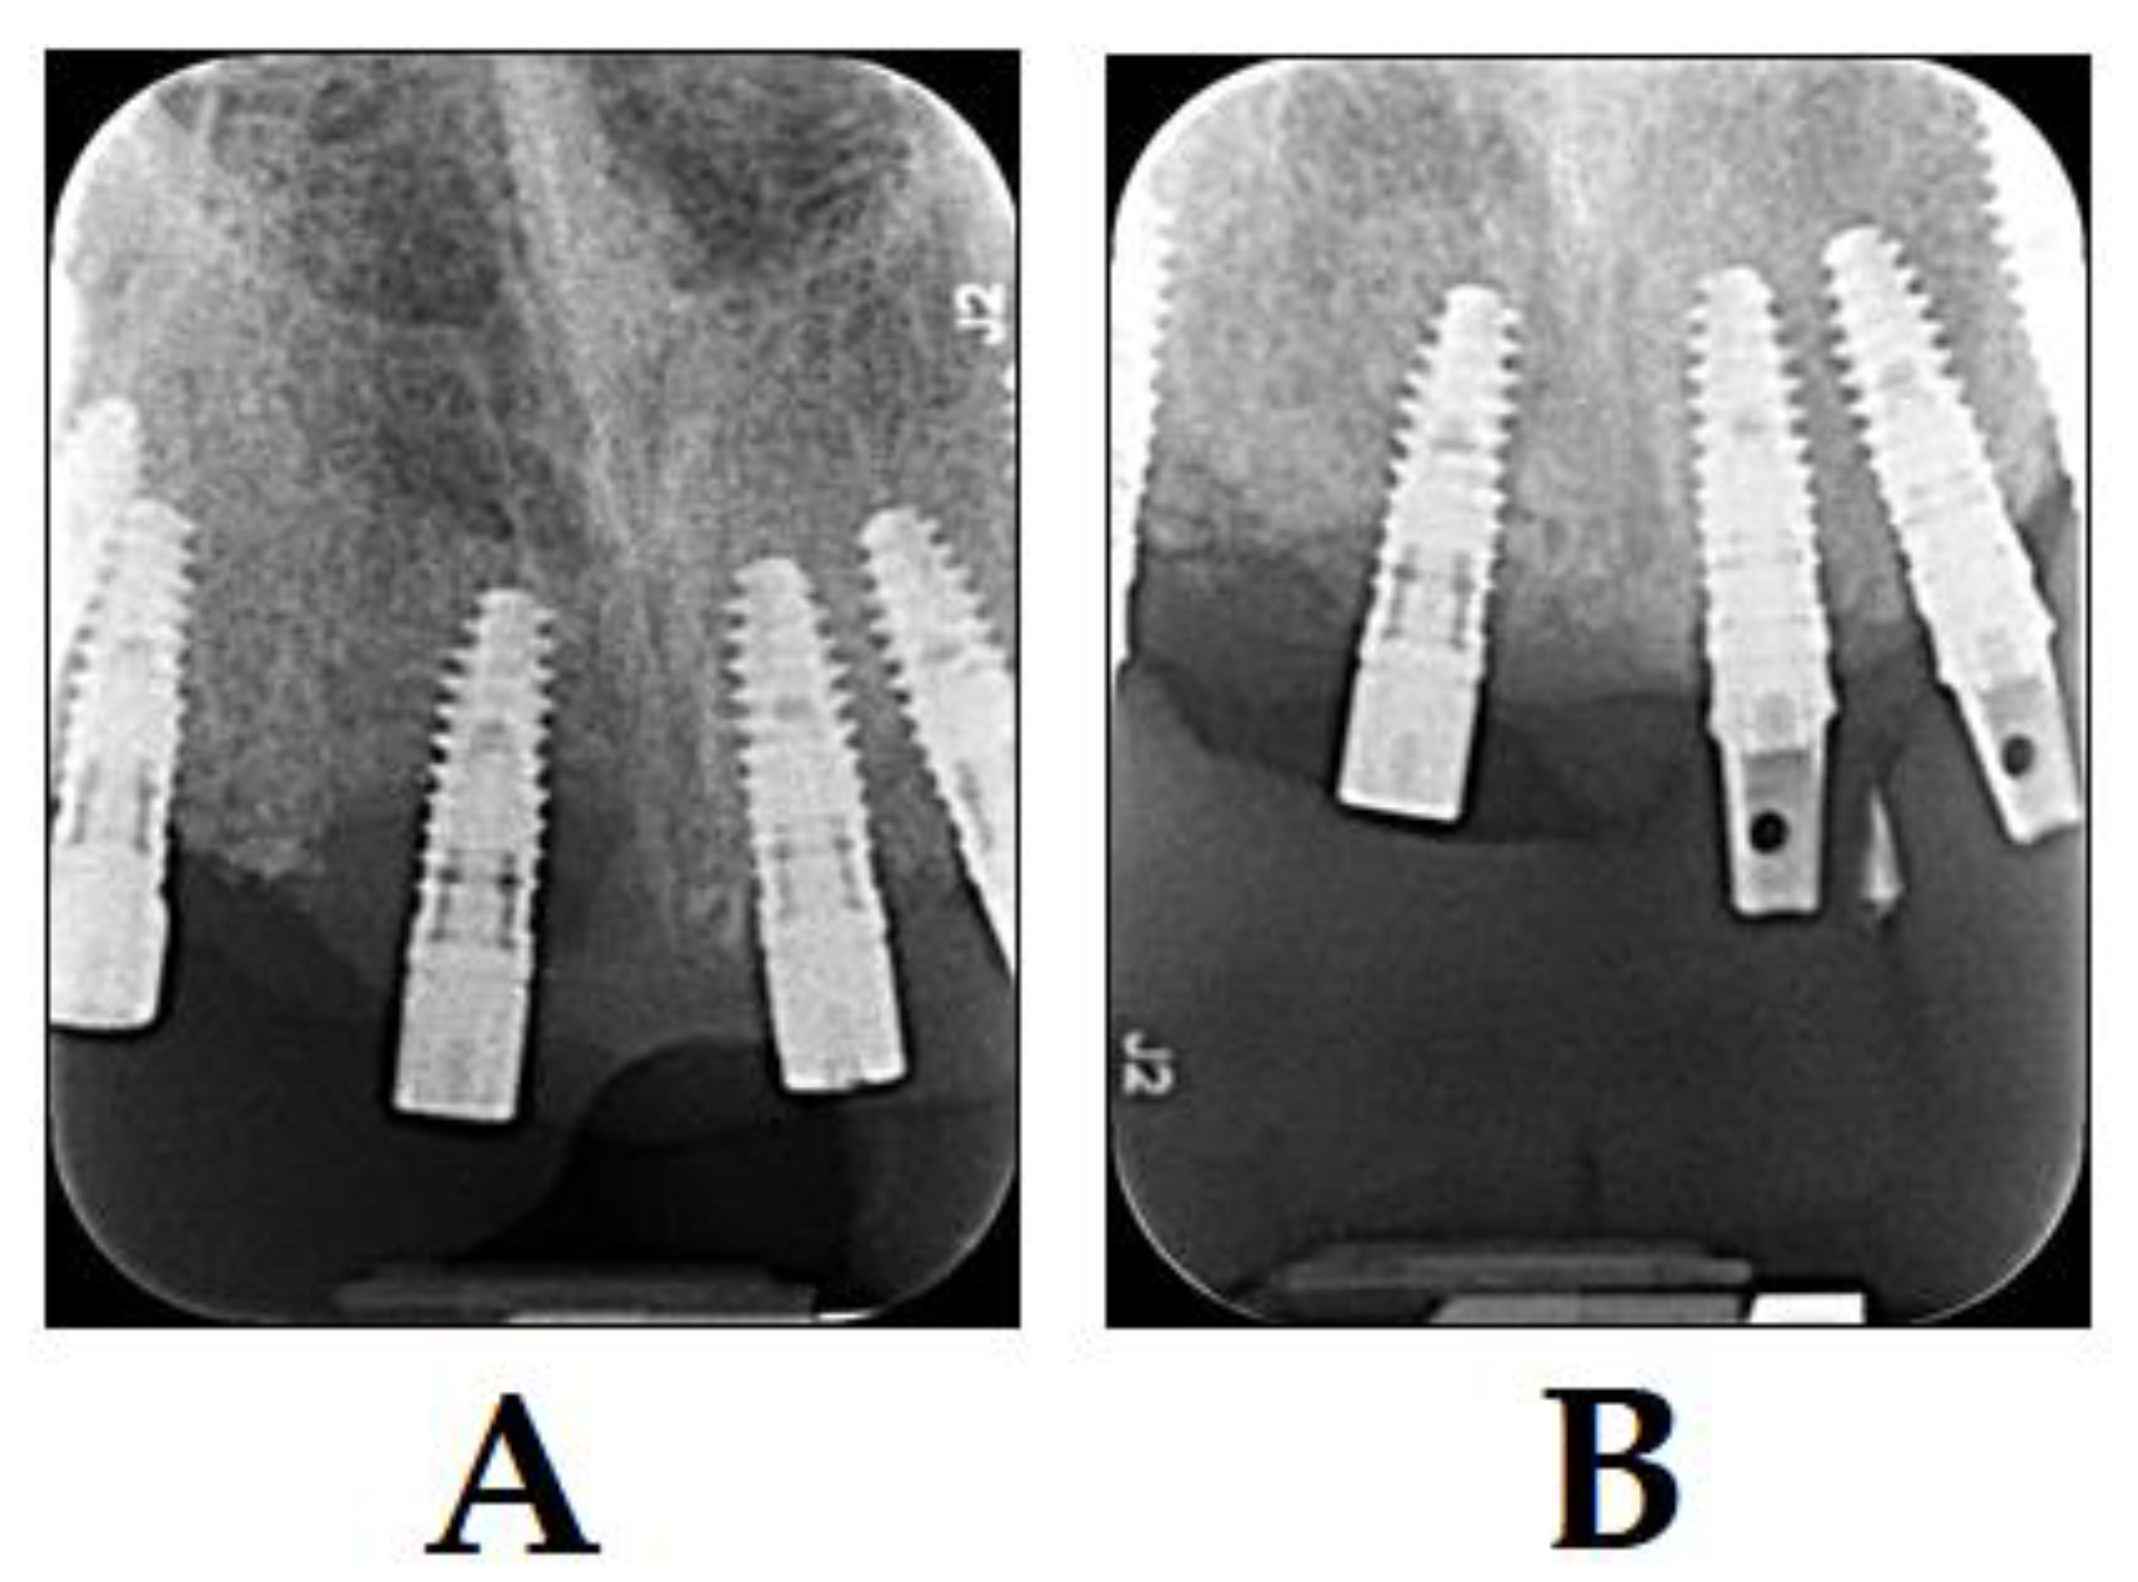

3.5. PDT in Implantology

- Khammissa, R.A.G.; Feller, L.; Meyerov, R.; Lemmer, J. Peri-implant mucositis and peri-implantitis: Bacterial infection. SADJ 2012, 67, 70, 72–74. [Google Scholar]

- Prathapachandran, J.; Suresh, N. Management of peri-implantitis. Dent. Res. J. (Isfahan) 2012, 9, 516–521. [Google Scholar] [CrossRef]

- Dörtbudak, O.; Haas, R.; Bernhart, T.; Mailath-Pokorny, G. Lethal photosensitization for decontamination of implant surfaces in the treatment of peri-implantitis. Clin. Oral Implants Res. 2001, 12, 104–108. [Google Scholar] [CrossRef]

- Sivaramakrishnan, G.; Sridharan, K. Photodynamic therapy for the treatment of peri-implant diseases: A network meta-analysis of randomized controlled trials. Photodiagnosis Photodyn. Ther. 2018, 21, 1–9. [Google Scholar] [CrossRef]

- Esposito, M.; Grusovin, M.G.; De Angelis, N.; Camurati, A.; Campailla, M.; Felice, P. The adjunctive use of light-activated disinfection (LAD) with FotoSan is ineffective in the treatment of peri-implantitis: 1-year results from a multicentre pragmatic randomised controlled trial. Eur. J. Oral. Implantol. 2013, 6, 109–119. [Google Scholar]